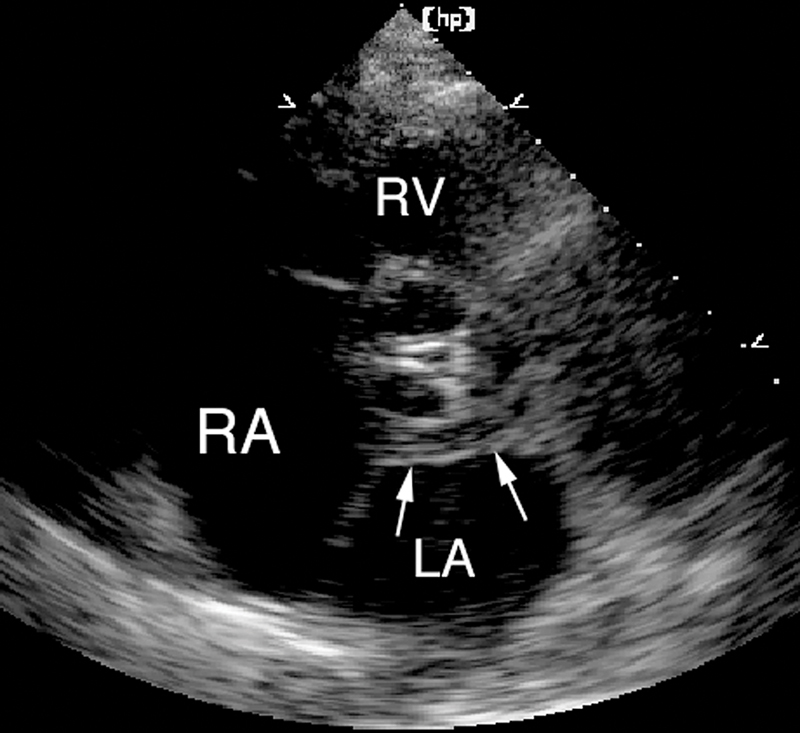

فحوصات تشخيصية لبعض امراض القلب والشرايين التاجية